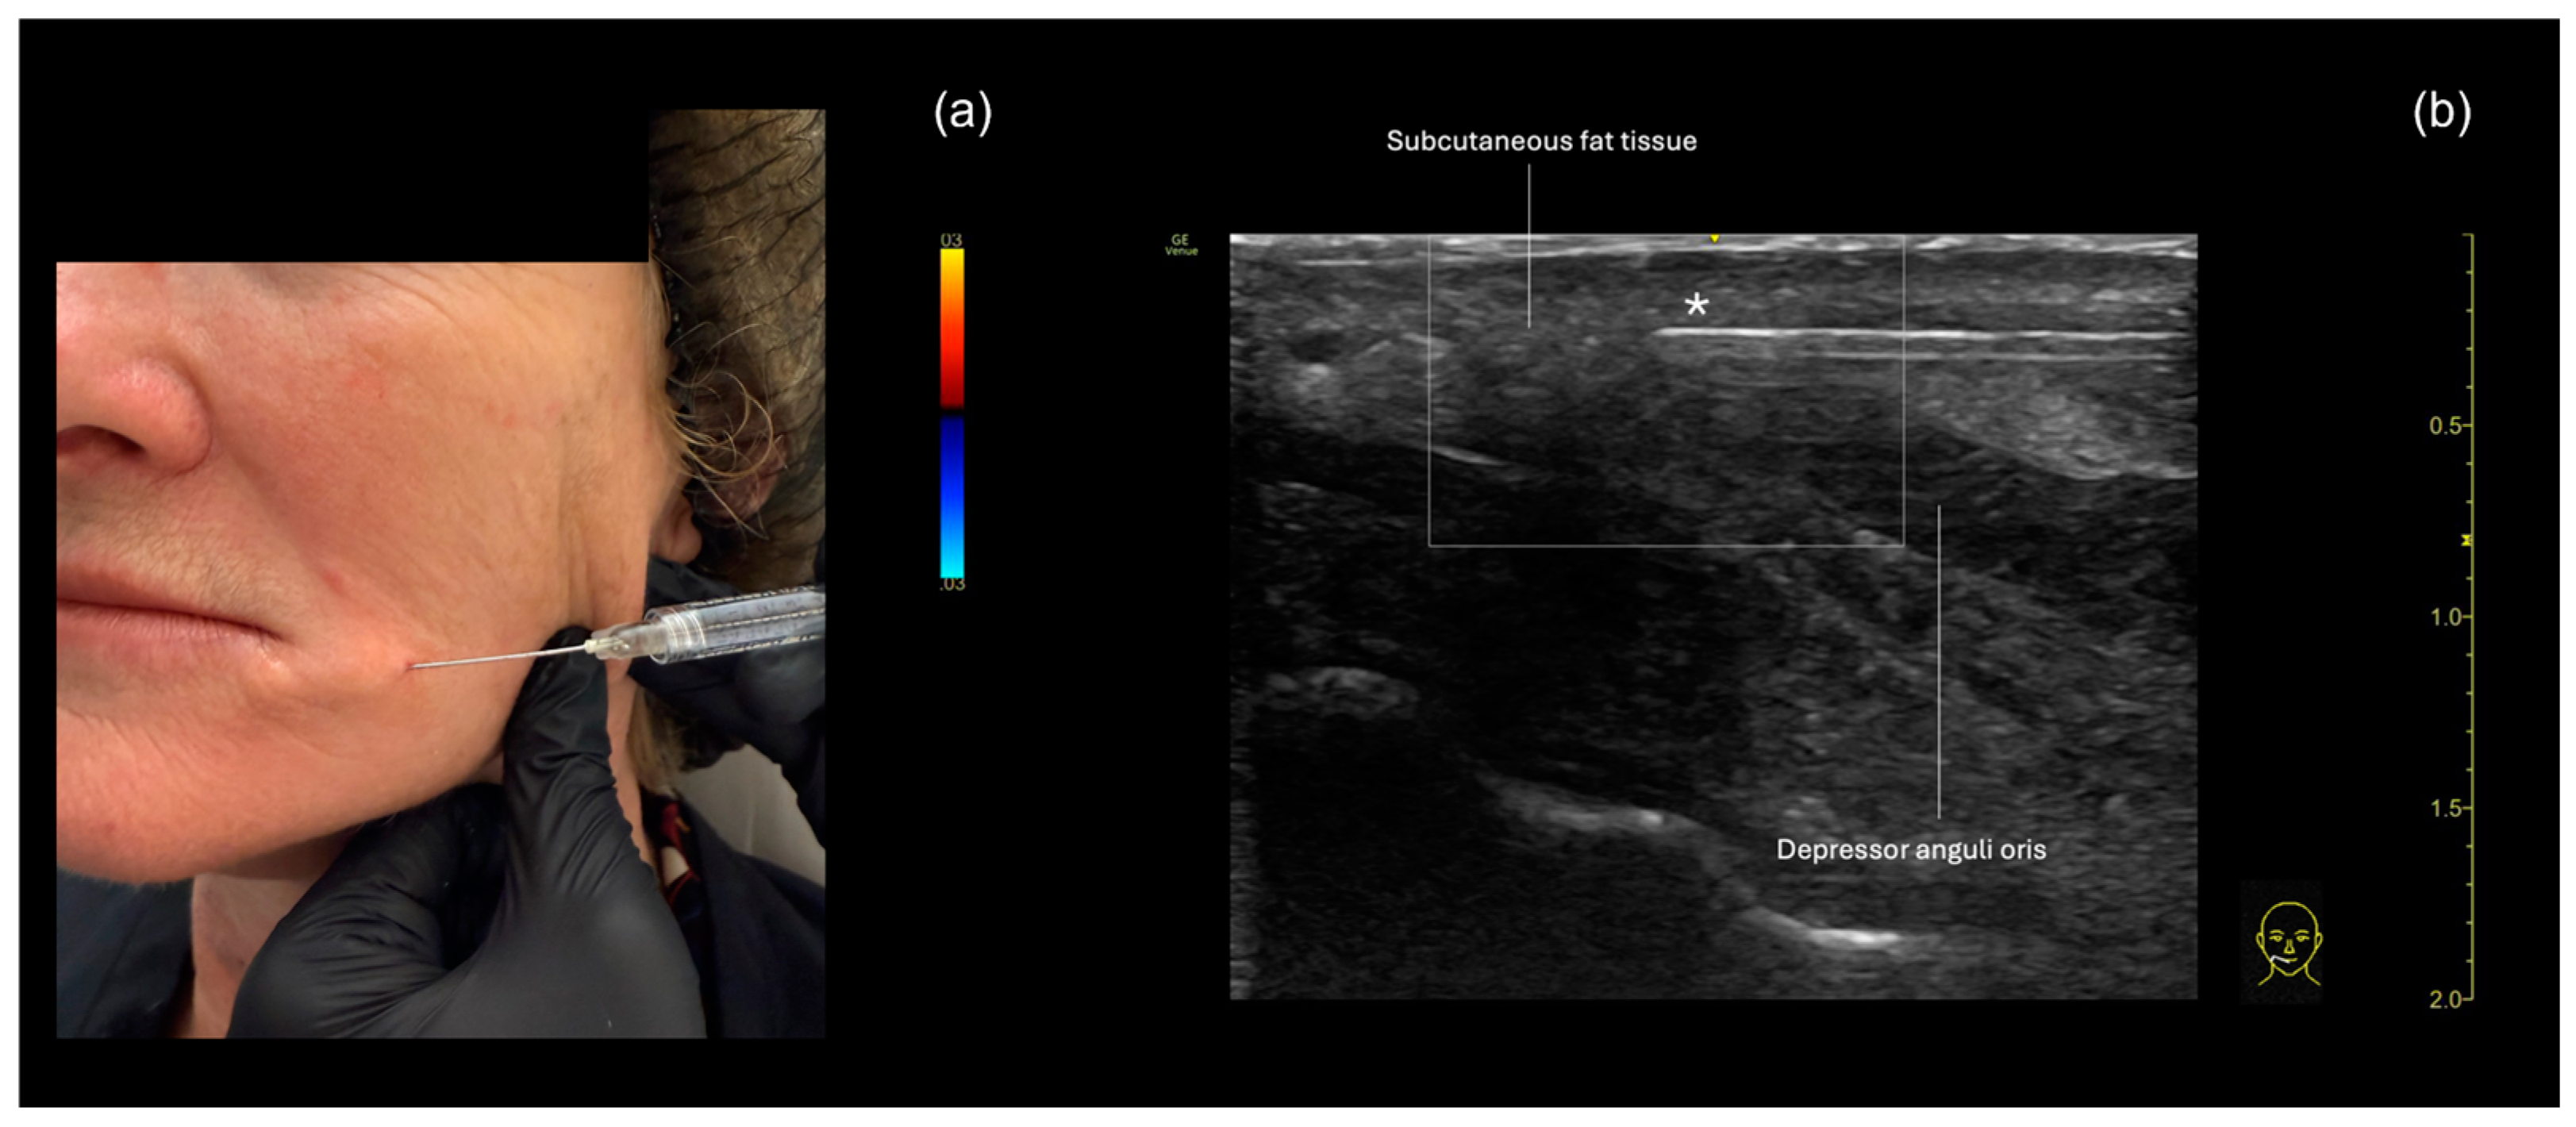

3.2. Labiomandibular Folds or Marionette Lines

Ultrasound-Guided Filling Techniques of the Marionette Line

- Subcutaneous filler placement with a blunt cannula

- Submuscular filler placement with a blunt cannula